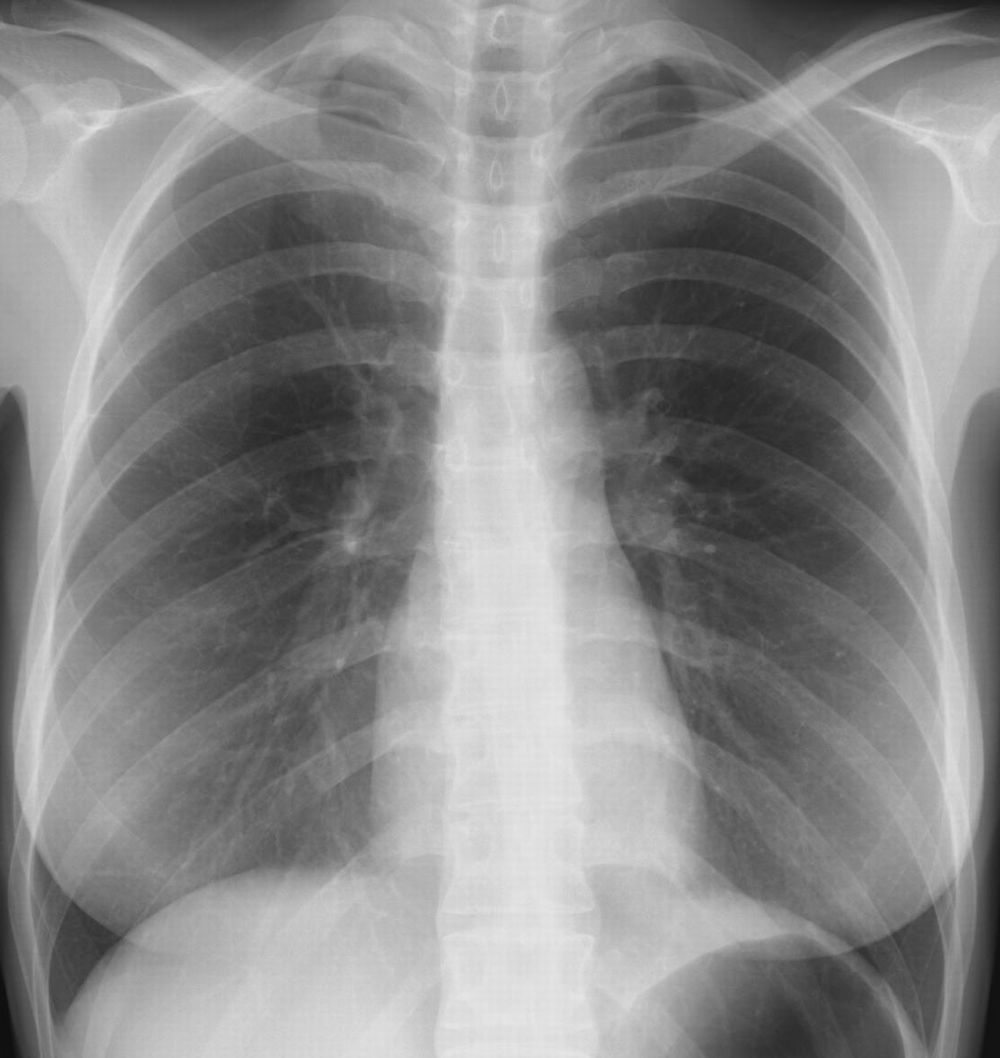

(シルエットサインの読み方) 典型的な均等影の所見、侵されている肺区域を考慮する時、右心辺縁は鮮明にみることができシルエットサイン陰性、右の横隔膜は不鮮明でシルエットサイン陽性のためこの均等影はS8とS10にあることが断定できる(写真からはS7、9も含まれて下葉全体に及ぶ肺炎と推定可能)。